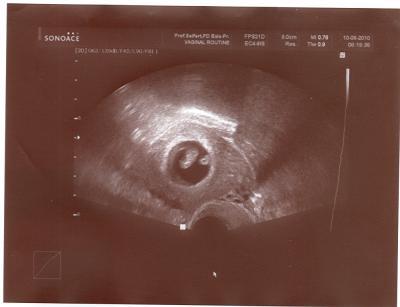

Hallo Mädels, hier mal ein US-Bild von meinem Krümel von Dienstag! Freu mich auf kommenden Di., da hab ich wieder US!!!! Schönes WE, Bine

Schön! Es ist doch einfach immer wieder wundervoll, diese kleinen Krümel zu sehen... LG Tina